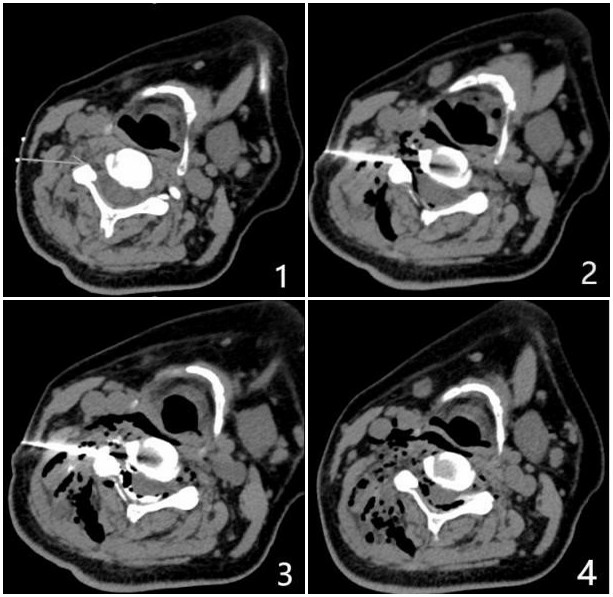

Figure 3. MRN examination of brachial plexus in cervical spondylotic radiculopathy. (A, B, C) coronal T2-TDEAL images; (D) Axial T2WI showed that the right intervertebral foramen of C4/5 intervertebral disc protruded; (E) T2WI sagittal position; The signal of right C5 and C6 nerve roots and corresponding segments of brachial plexus was significantly higher than that of left side (long arrow A, B, C). At right C4/5 and C5/6, herniation of intervertebral disc and stenosis of corresponding intervertebral foramen can be seen (short arrows D, E).